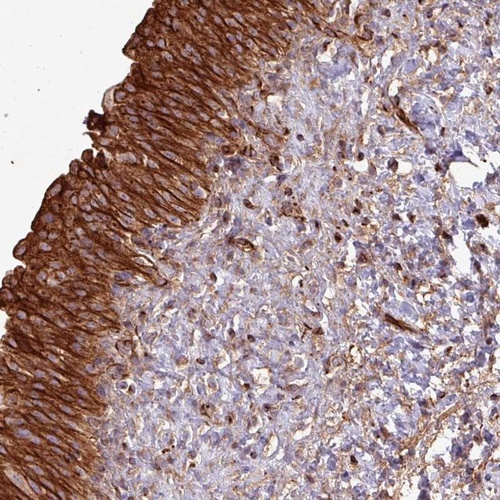

Immunohistochemical staining of human urinary bladder shows strong cytoplasmic and membranous positivity in urothelial cells.